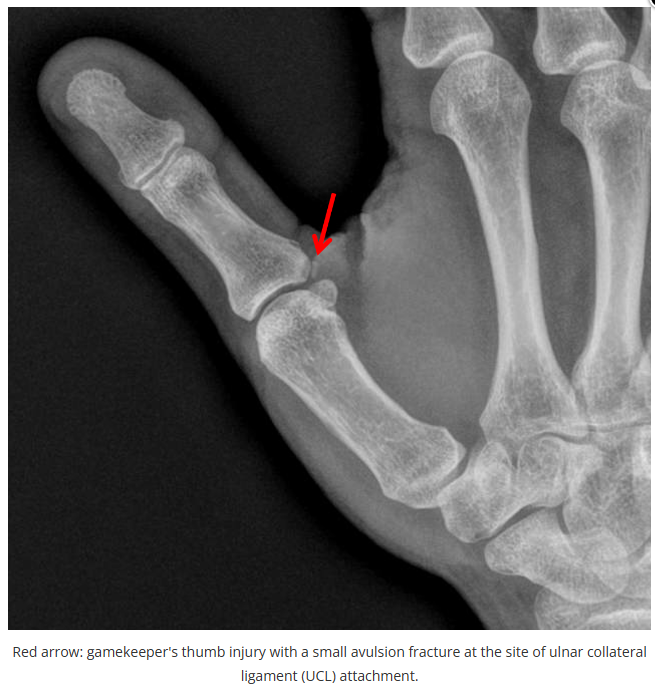

今天是腕部与手的X线片。所有X线片都

带有标注和说明

,可以选择长按图片,

自动翻译相关说明

。

进阶篇